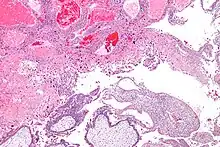

Micrograph of intermediate trophoblast, decidua and a hydatidiform mole (bottom of image). H&E stain.